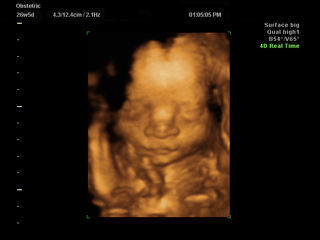

موجات فوق صوتية ثلاثية الأبعاد

يمكن لصور الموجات الصوتية ثلاثية الأبعاد أن توفر لكم صور لمراحل نمو الجنين بالصور، بجودة تفاصيل عالية للجنين. هذا النوع من الموجات الصوتية يمكن أن يُساعد طبيبكم في بعض الأحيان على تقييم نمو وتطور الجنين. الموجات فوق الصوتية ثلاثية الأبعاد متوفرة أيضًا تجاريًا، ولكن لا يُنصح باستعمال الموجات فوق الصوتية لغرض الحصول على الصور التذكارية فقط.